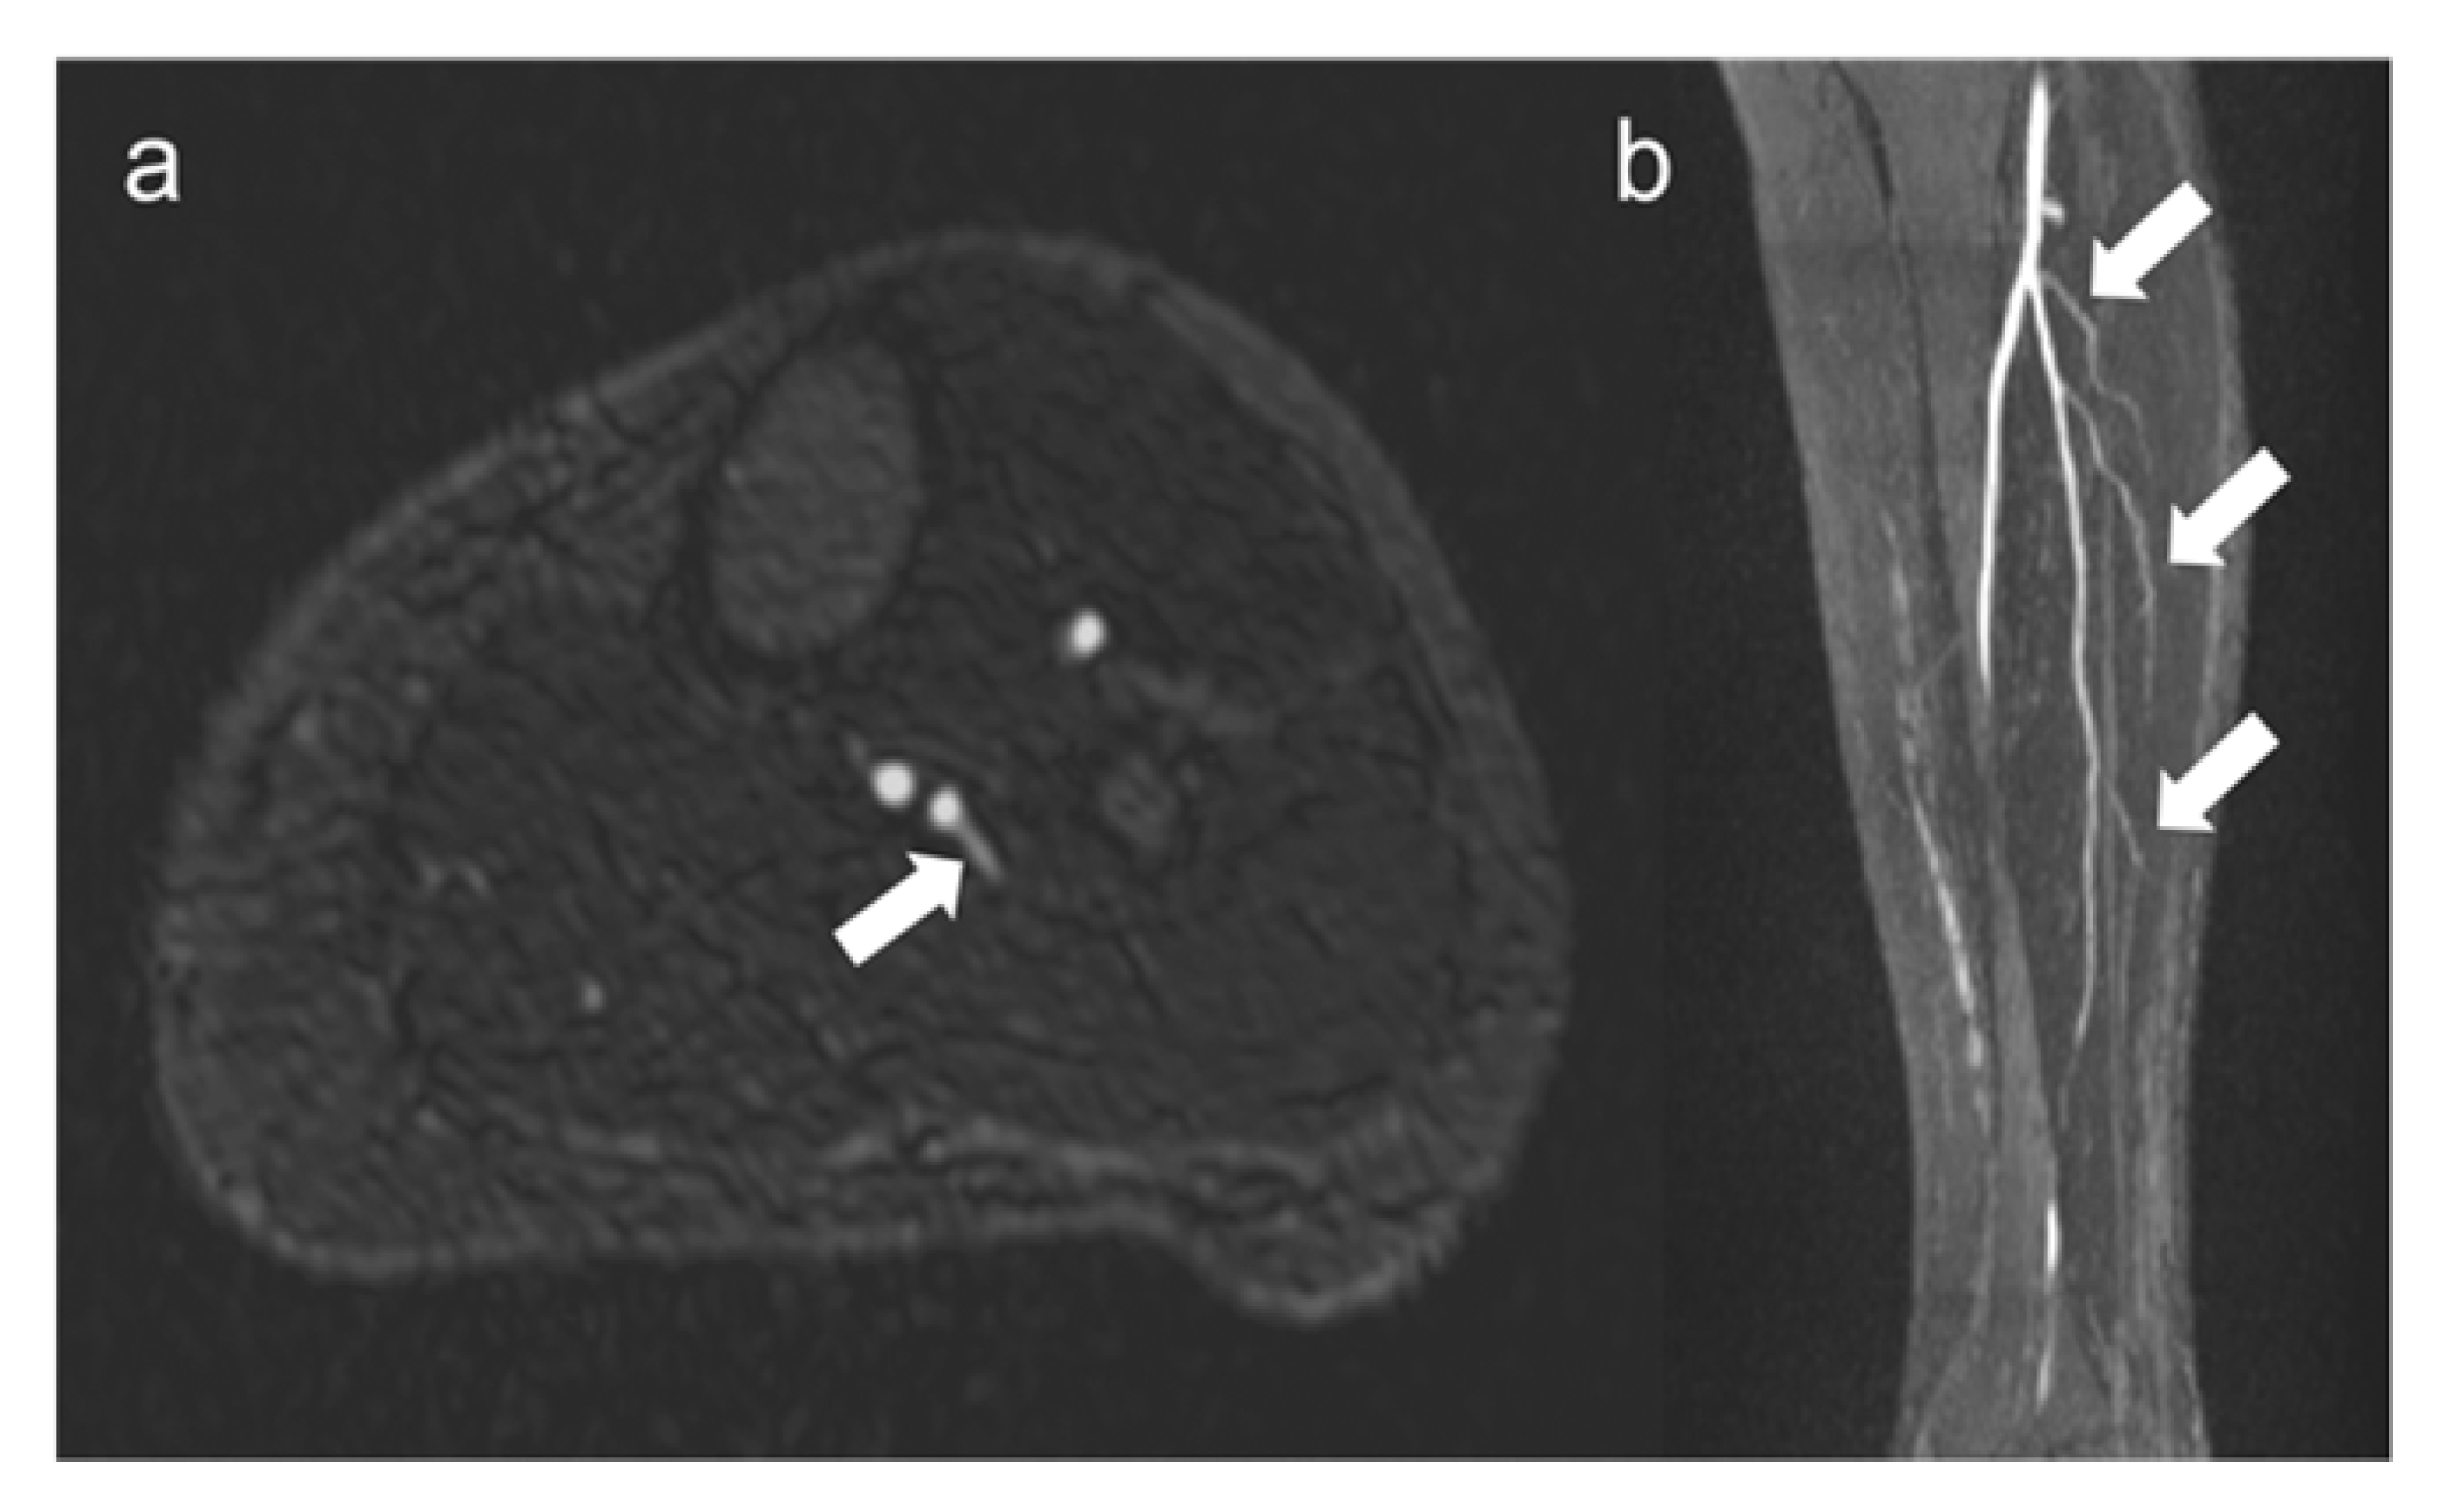

Figure 4.

Visualization of fibular perforators using QISS-MRA. In panel (a), the exit of a fibular perforator is seen in transverse view (white arrow). In panel (b), three fibular perforators can be seen in sagittal view (white arrows). The images belong to two different patients.